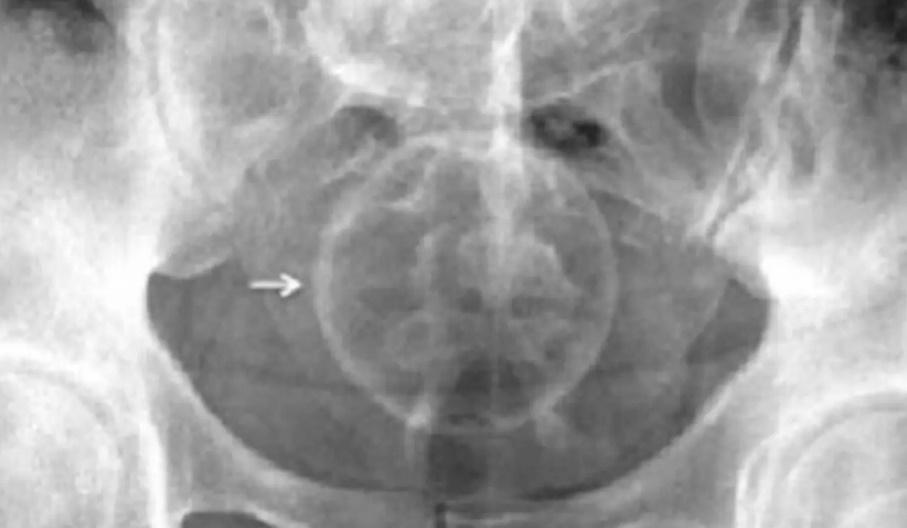

綜合報道,婦科女醫生Sarah Welsh近日應診時發現,聖誕裝飾品卡在下體的個案突然大增,令她決定出面呼籲大眾:「將聖誕飾物塞進下體是不可取的行為」,當中更有士的糖、裝飾球卡布陰道的個案。Sarah Welsh語重深長勸說:「任何含糖份的物件都應該遠離陰道,除了糖果易碎容、易折斷,糖製品也有可能破壞陰道內微生物環境,導致私處感染」。她又指,裝飾品表面亦可能鋒利或有碎片,容易弄傷下體,導致使用者疼痛或是受傷。

報道指,根據英國國家電子傷害系統監測(NEISS)數據,英國2021年25歲至64歲成人把裝飾物塞進體內的案件,竟然高達13,213宗。Sarah Welsh建議,市面上其實有許多合格又通過認證的性商品,相信可以讓民眾使用時達到更好的效果。